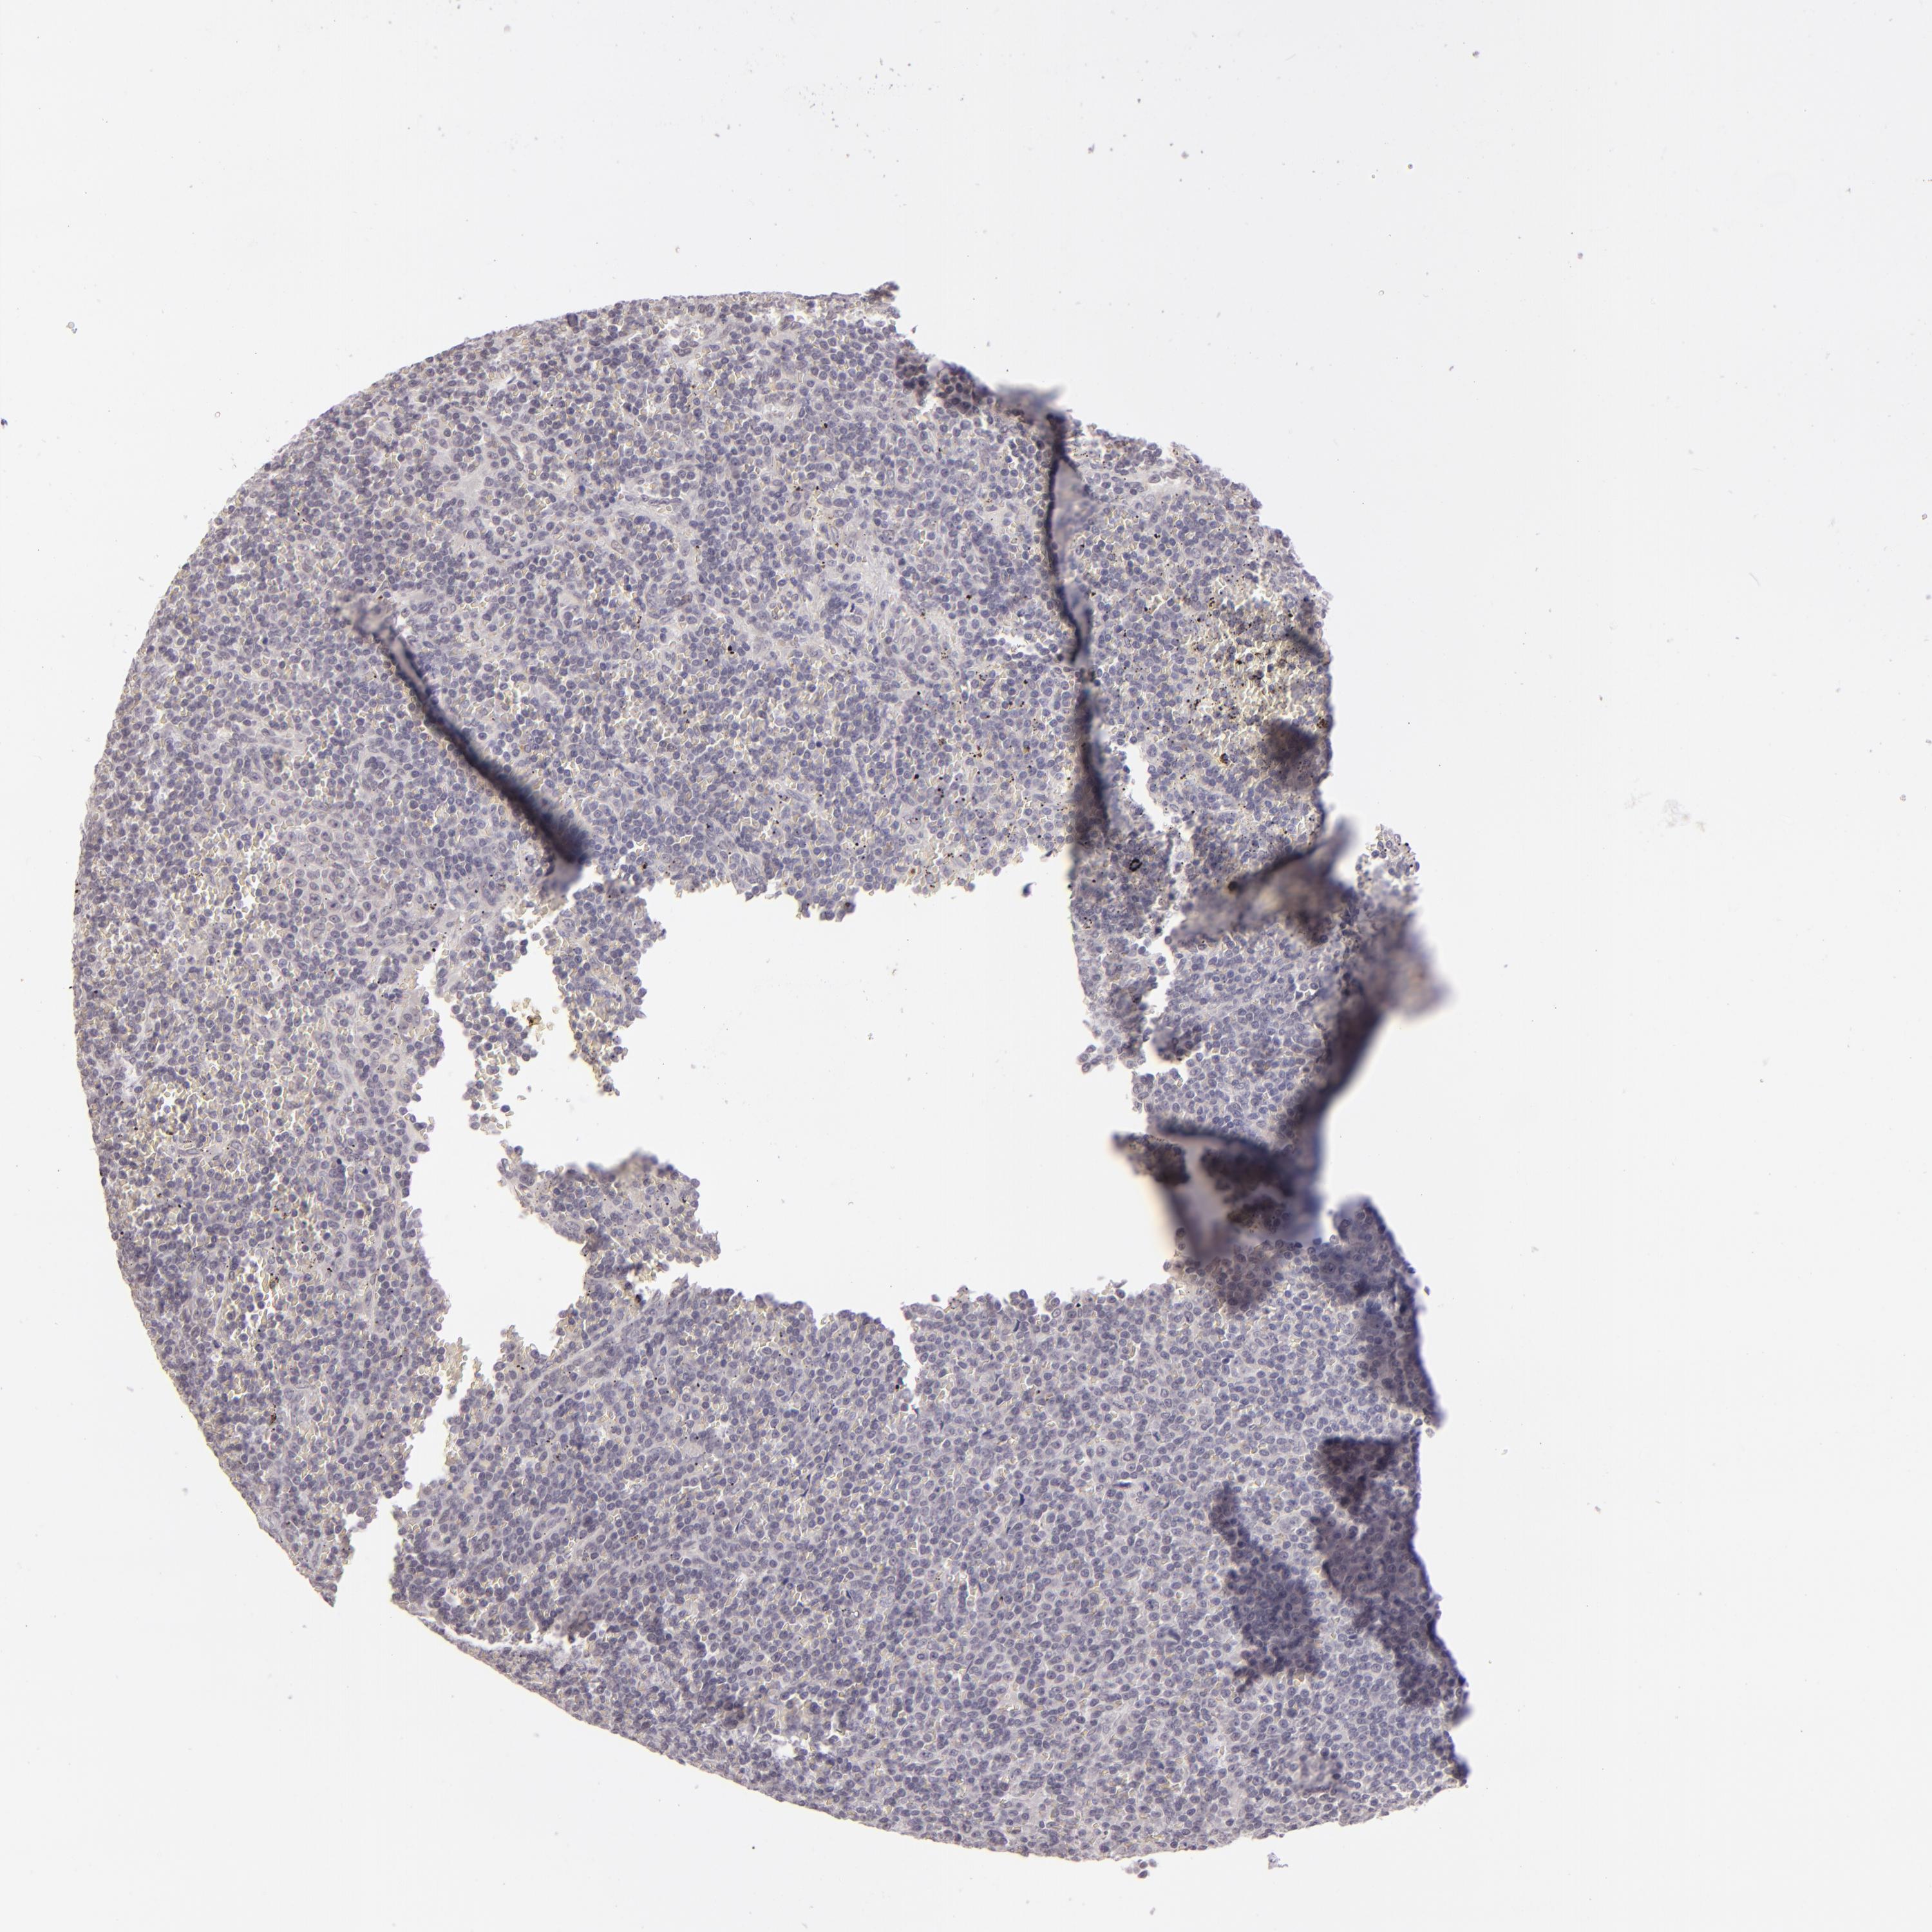

LYMPHOMA - Protein expressioni

A mouse-over function shows sample information and annotation data. Click on an image to view it in a full screen mode. Samples can be filtered based on level of antibody staining by selecting one or several of the following categories: high, medium, low and not detected. The assay and annotation is described here.

Each image is clickable and will lead to virtual microscopy that enables deeper exploration of all samples and also displays staining intensity scores, fraction scores and subcellular localization as well as patient and tissue information for each sample.

Antibody HPA001791

Staining

High

Medium

Low

Not detected

Intensity

Strong

Moderate

Weak

Negative

Quantity

>75%

75%-25%

<25%

None

Location

Nuclear

Cytoplasmic/membranous

Cytoplasmic/membranous,nuclear

Malignant lymphoma, non-Hodgkin's type, High grade

Hodgkin's disease, NOS

Malignant lymphoma, non-Hodgkin's type, Low grade